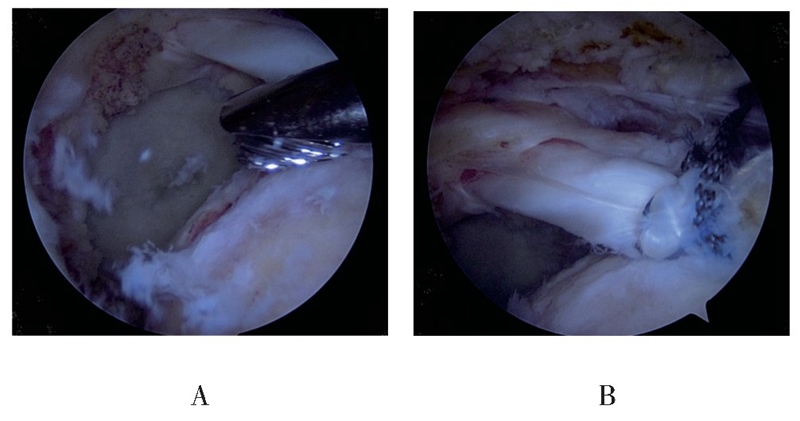

(2)以骨性刨削器磨除肱骨大结节骨赘,清理肩袖足印区,合适张力下将LHBT转位至冈上肌腱足印区近关节面处,一般后移1.5cm左右,植入一枚直径5.5mm Healix带线锚钉(Mitek,三线锚钉),Lasso技术固定移位LHBT(见图2)。

图2 骨性刨削清理冈上肌腱足印区(A),移位固定LHBT至冈上肌腱足印区(B)